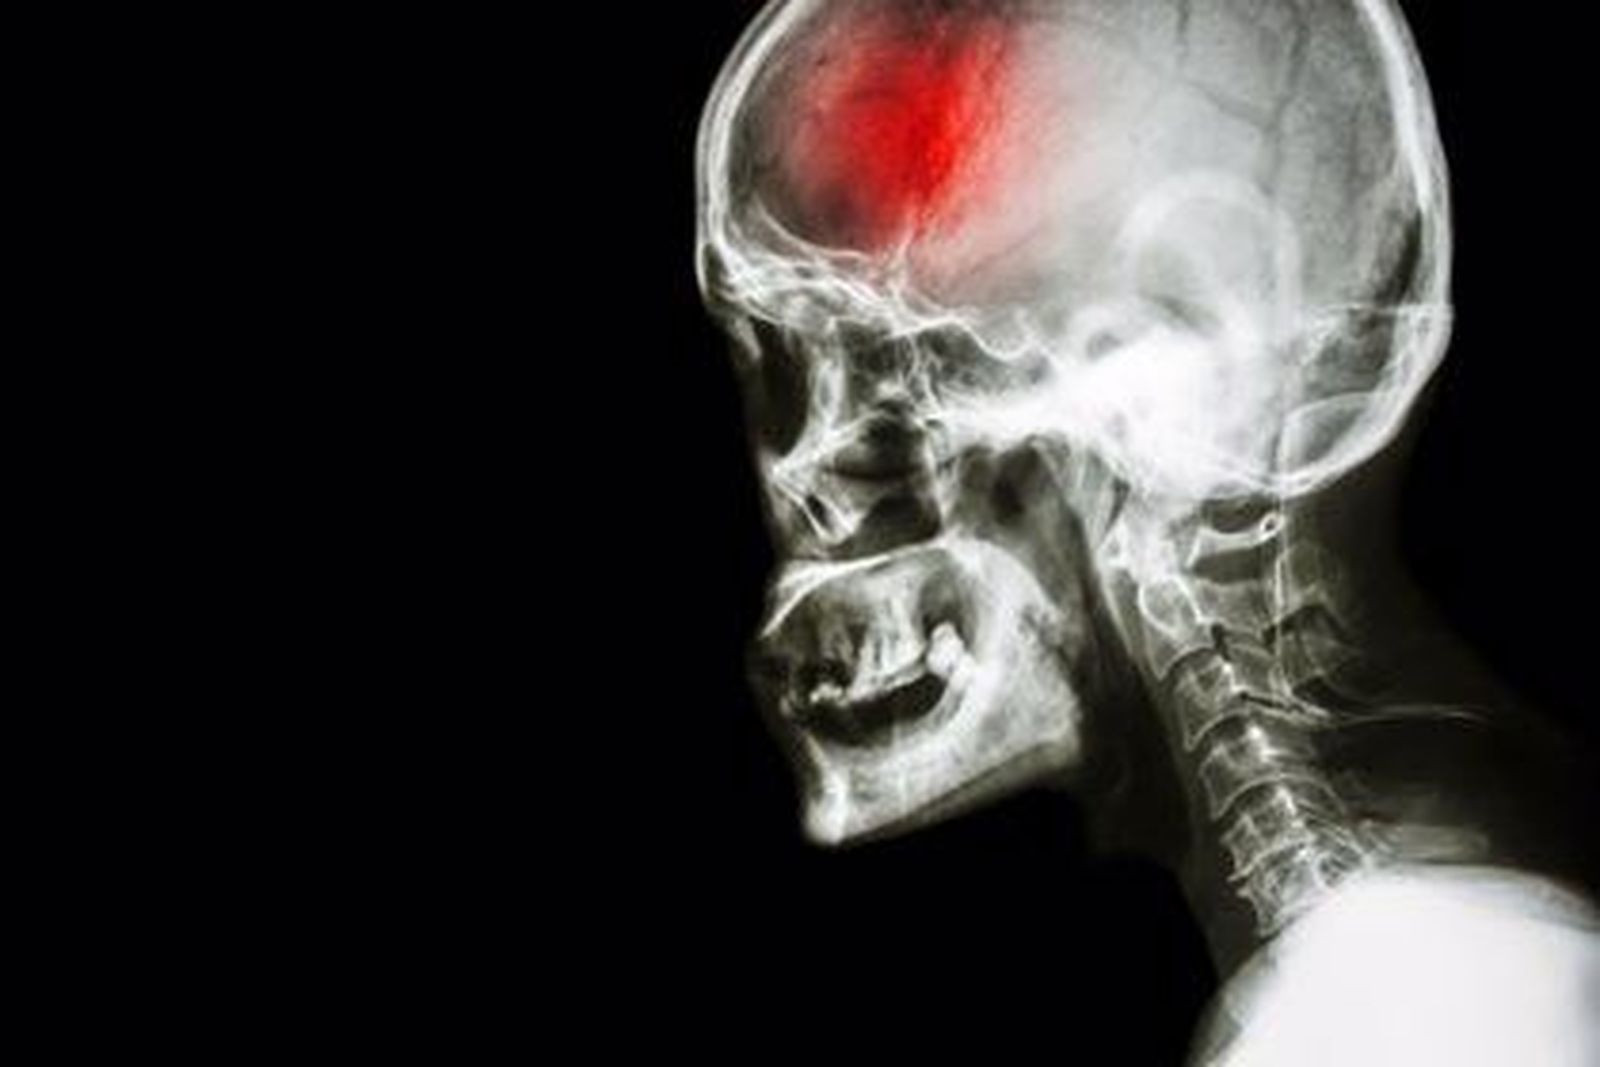

La afasia es una de las enfermedades que más se desconocen, pero que cada vez es más común entre los diagnósticos. Padecida por Bruce Willis, puede estar producida por hasta cinco tipos de enfermedades distintas y afectar así a diferentes partes del cerebro. De hecho, la progresiva primaria, que afecta a un 70% de la población, puede derivar en un ictus. Tal y como se ha concluido en un nuevo estudio de la Universidad Northwestern Medicine, "la enfermedad ataca el área responsable de la gramática y al área responsable de la comprensión de palabras" como consecuencia de una lesión o una alteración en el funcionamiento en las partes del cerebro responsables de la expresión, la comprensión, la lectura y/o la escritura.

Según se publica en el periódico ABC, en función de las áreas cerebrales en las que se localice la lesión y del grado de estas lesiones, la afasia puede tener distintos tipos de gravedad y el paciente manifestará problemas diferentes en el lenguaje. Si hay algo que caracteriza a la enfermedad, es que, a menudo, se diagnostica erróneamente en las primeras etapas, perdiendo la oportunidad de recibir tratamiento

En el 40% de los casos de afasia, la enfermedad subyacente es una forma muy inusual del alzhéimer. En el 60% de los casos, las enfermedades que causan la afasia pertenecen a la degeneración lobar frontotemporal. Aunque la mayoría de la gente no ha oído hablar de esto, las condiciones de degeneración del lóbulo frontotemporal son responsables de aproximadamente el 50% de todas las demencias que comienzan antes de los 65 años.